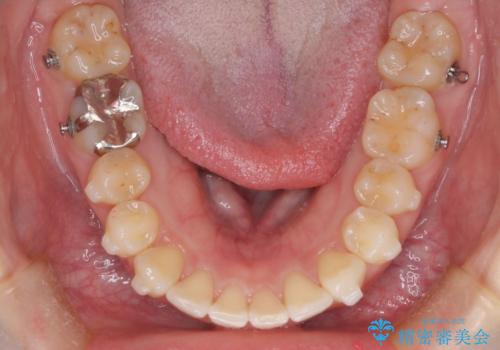

【インビザライン】前歯が出てるのを治したい

- 前歯の凸凹と前突を主訴に来院されました。

インビザラインにて治療をおこない、歯並びを改善することができました。